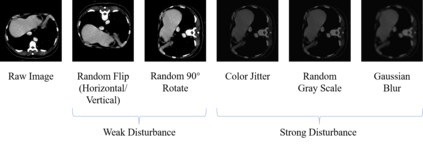

Machine learning models for medical images can help physicians diagnose and manage diseases. However, due to the fact that medical image annotation requires a great deal of manpower and expertise, as well as the fact that clinical departments perform image annotation based on task orientation, there is the problem of having fewer medical image annotation data with more unlabeled data and having many datasets that annotate only a single organ. In this paper, we present UniMOS, the first universal framework for achieving the utilization of fully and partially labeled images as well as unlabeled images. Specifically, we construct a Multi-Organ Segmentation (MOS) module over fully/partially labeled data as the basenet and designed a new target adaptive loss. Furthermore, we incorporate a semi-supervised training module that combines consistent regularization and pseudolabeling techniques on unlabeled data, which significantly improves the segmentation of unlabeled data. Experiments show that the framework exhibits excellent performance in several medical image segmentation tasks compared to other advanced methods, and also significantly improves data utilization and reduces annotation cost. Code and models are available at: https://github.com/lw8807001/UniMOS.